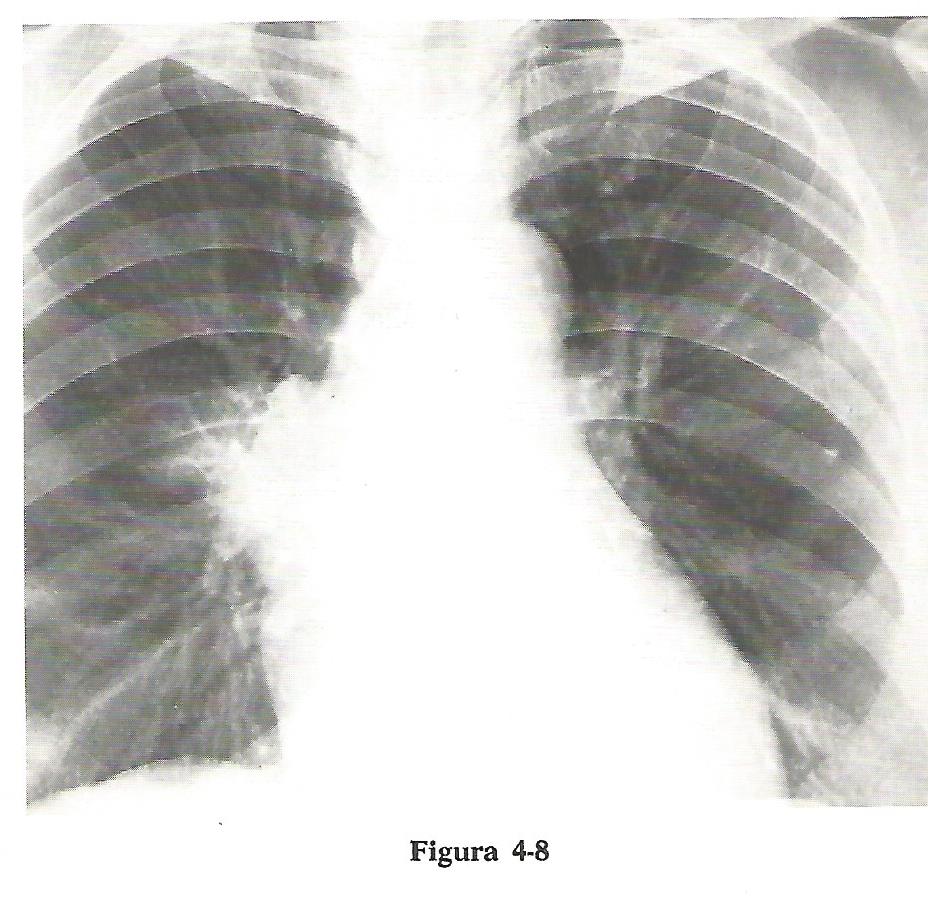

La porción más alta del borde cardiaco derecho y la aorta ascendente están en contacto anatómico con el segmento anterior del lóbulo superior derecho o LSD (2). Si el borde cardiaco derecho y la aorta ascendente son anteriores, el segmento anterior del lóbulo superior derecho (LSD) (2) es anterior.

De esta forma: La aorta ascendente y la porción superior del borde cardiaco derecho están en contacto con el segmento anterior del lóbulo superior derecho (LSD) (2).

Un proceso patológico en el segmento anterior del lóbulo superior derecho puede borrar tanto la aorta ascendente como el borde cardiaco derecho o ambos.

La figura 4-8 nos muestra la desaparición del borde cardiaco derecho y de la aorta ascendente por una neumonía del segmento anterior del lóbulo superior derecho (LSD). Felson et al